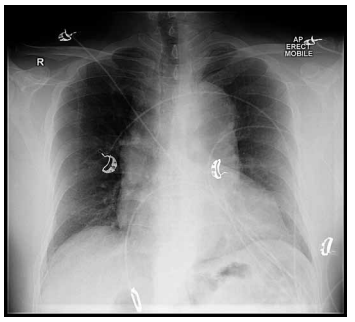

Mulher, 65 anos, com histórico de hipertensão tratada com hidroclorotiazida, apresenta-se com dispneia e dor torácica intensa irradiada para as costas. O exame físico inicial revela pressão arterial de 205 × 98 mmHg, estertores pulmonares em bases e alterações inespecíficas do segmento ST no eletrocardiograma. A radiografia de tórax está ilustrada a seguir:

Enunciado 4918745-1 (Arquivo pessoal; imagem usada com autorização)